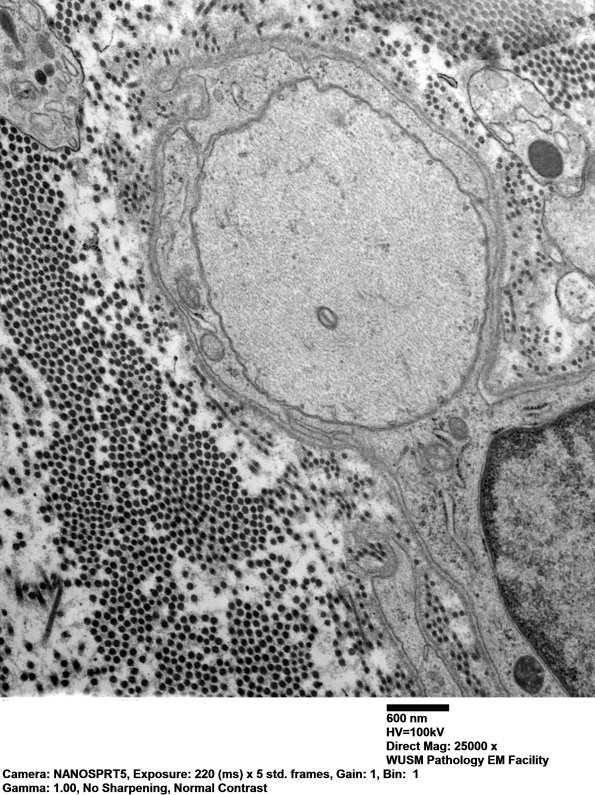

3B4,5 The number of demyelinated axons is significantly greater than anticipated from the one micron plastic sections. (electron micrographs)